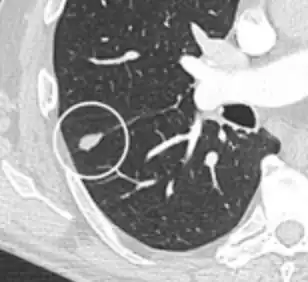

Nodule with pleural retraction.[9] -

In this case, pleural retraction is seen as a triangular fat component.[9]